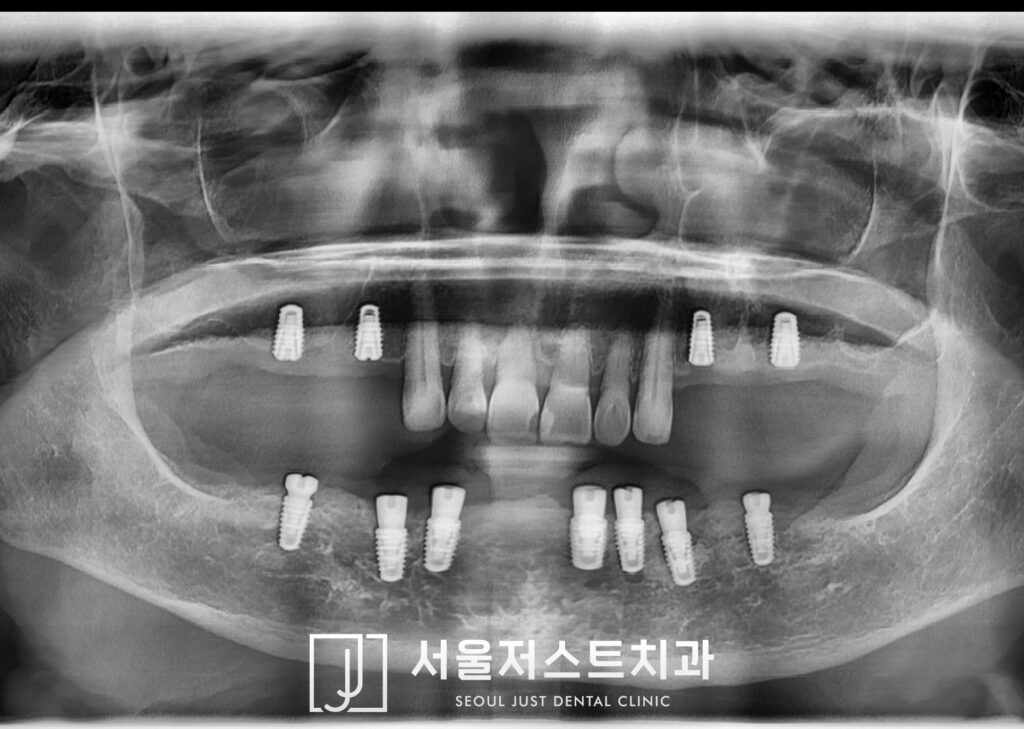

처음 내원하셨을 때의 사진을 보면

장기간 틀니 사용으로 인해

위쪽의 상악동 주변 뼈가 2mm 정도로

매우 얇은 것으로 관찰되어

임플란트 식립이 어려운 상황이었으며

아래쪽도 마찬가지로 잔존 잇몸뼈가

많이 흡수된 상태로 큰 신경관인

하치조 신경과 매우 가까운 상황이었습니다.

남아 있는 앞니 또한 심한 치주염으로 인해

발치가 필요한 상황을 자제분과 함께

충분히 설명드렸는데요.